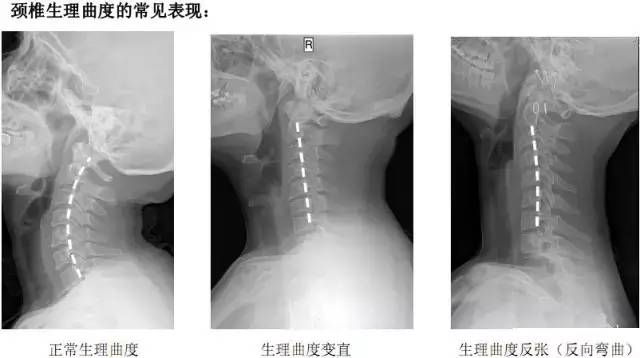

什么是颈椎反弓?

正常颈椎呈现“C”形向前的生理弧线,它既保证了颈椎活动的高度灵活性,又减轻了颈椎间盘的重力负荷,使颈椎处于最佳的力线状态下工作。如果没有生理弯曲,颈椎会出现僵直,甚至向相反的方向弯曲,就称为颈椎反弓。

卧床看书、看电视,高枕卧床看书,睡觉时不适当使用“高枕”,卧高靠背看电视以及长时间上网、搓麻等不良的生活习惯,使头部前屈,导致其曲线前凸日渐减少,变直甚或反弓。“颈椎反弓”现象在普通X光片甚至医生的体检中都很容易被发现,近年来逐渐呈低龄化趋势,应引起低头族的重视。